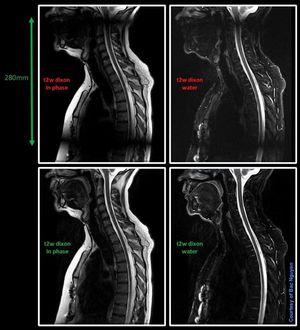

MR Spine Imaging – FastDixon @ Siemens 1.5T Aera Fast dixon option is great, but remember use it with care. Upper row images fast dixon was on, but FOV phase had over 100%. In other words, I used 280mm FOV, but acquired 370mm by using over 100% FOV phase. Seems like fast dixon option can’t handle this for spine imaging in sagittal plane. Lower row, same acquired FOV 370mm, but fast dixon option OFF. Just a reminder if you get such artifacts.